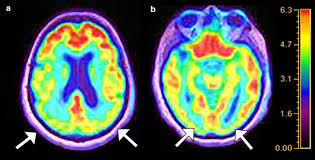

טיפול באור בתדרי גאמא בקליניקת NRI הטכנולוגיה החדשנית לשיקום קוגניטיבי, רגשי ונוירולוגי רקע מחקרי מחקרים מהשנים האחרונות מצביעים על כך שגירוי אור בתדר 40Hz יכול לסנכרן גלי גאמא ...

קרא עוד...